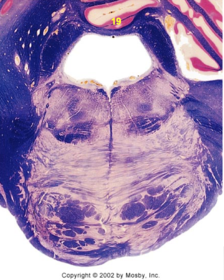

| Medullary pyramids | |

| Hypoglossal nucleus | |

| Hypoglossal nerve | |

| Dorsal motor nucleus of X | |

| Nucleus ambiguus | |

| Solitary tract | |

| Solitary nucleus | |

| ALS | |

| Medial lemniscus | |

| Medial longitudinal fasciculus | |

| Anterior spinocerebellar tract | |

| CN IX | |

| Inferior cerebellar peduncle | |

| Inferior olivary complex | |

| Dorsal cochlear nucleus | |

| Inferior vestibular nucleus | |

| Medial vestibular nucleus | |

| Spinal nucleus of V | |

| Spinal tract of V | |